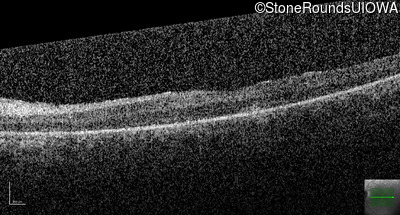

Optical Coherence Tomography - Right - 20/200 -1

Exemplar / OCT Stack